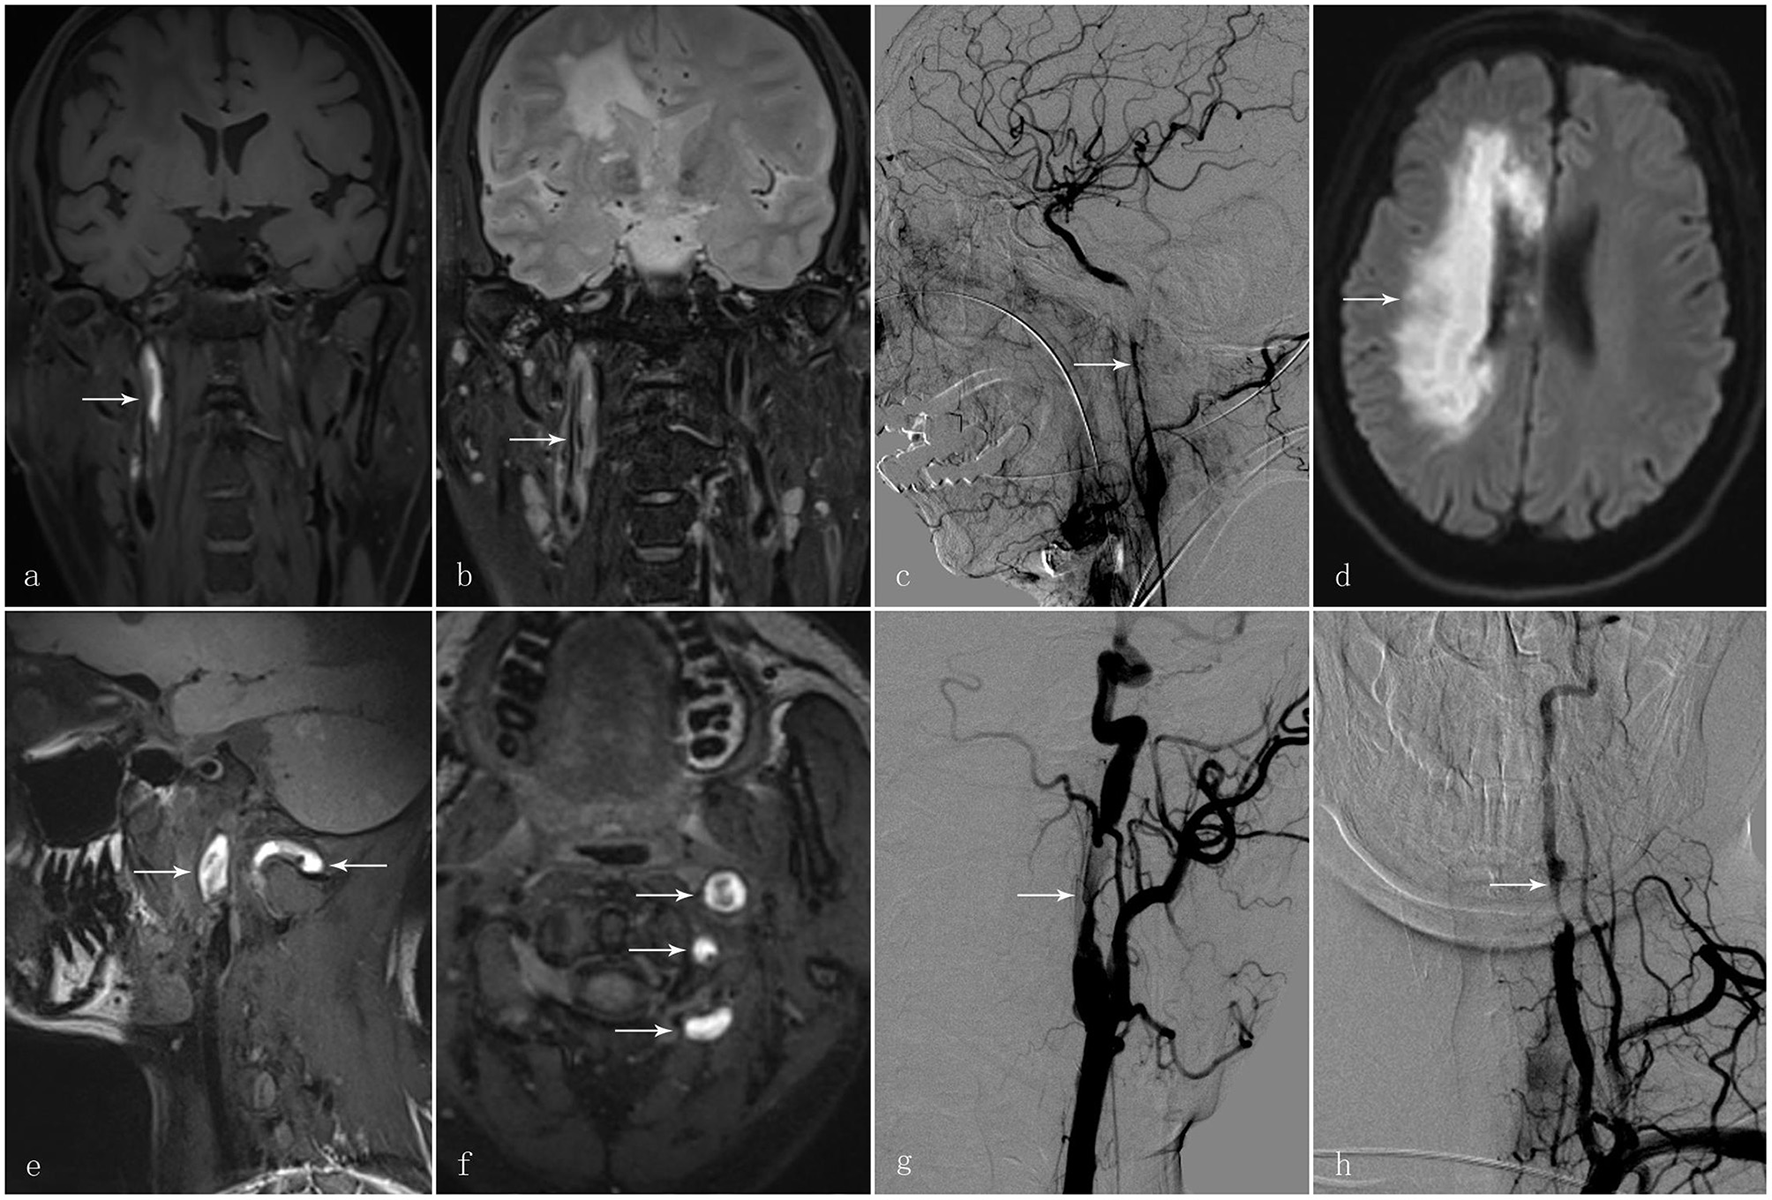

This retrospective study was approved by the Institutional Review Board of The First Affiliated Hospital of Sun Yat-sen University with written informed consent regarding data use for research purposes being obtained from each of 148 participants. In total, 148 participants diagnosed with CAD were selected via the medical record system of The First Affiliated Hospital of Sun Yat-sen University, between January 2010 and January 2020 with the diagnosis of CAD being confirmed by two stroke neurologists and a neuro-radiologist. The diagnostic confirmation of CAD was defined by the following criteria: intramural hematoma, intimal flap, double lumen, long tapering stenosis, artery occlusion that recanalised in an irregular aneurysmal dilation or stenosis, or irregular aneurysmal dilation with associated filiform and irregular stenosis on MRI and angiography (MRA), or CT angiography (CTA), or digital subtraction angiography (DSA) (1, 9). Two typical cases are illustrated in Figure 1.

Figure 1

A 58-year-old man presented with sudden-onset left hemiparesis and paraesthesia. (a) Coronal view of the high-resolution MRI T1 SPACE images showed an intramural hematoma at the C1 segment of the right internal carotid artery [(a); arrow]. (b) T2 images demonstrated intimal flap and double lumen in the corresponding vessel wall [(b); arrow]. (c) Digital subtraction angiography in the same patient showed long tapering stenosis at the C1 segment of the right internal carotid artery [(c); arrow]; (d) Diffusion-weighted imaging demonstrated an acute infarct in the territory of the right internal carotid artery [(d); arrow]. Another 30-year-old man presented with vertigo and vomiting after cervical manipulation. (e, f) The high-resolution MRI T1 SPACE images showed the intramural hematoma at the left internal carotid artery and vertebral artery [(e, f); arrows]. (g) Digital subtraction angiography displayed irregular long tapering stenosis at the C1 segment of the left internal carotid artery and V2 segment of the left vertebral artery [(g, h); arrow].